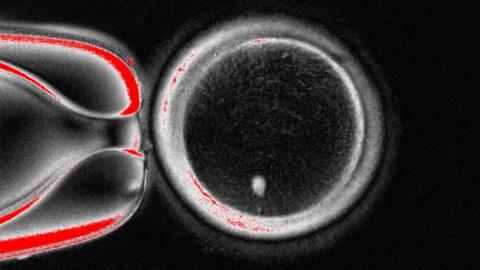

US scientists have, for the first time, made early-stage human embryos by manipulating DNA taken from people's skin cells and then fertilising it with sperm.

The technique could overcome infertility due to old age or disease, by using almost any cell in the body as the starting point for life.